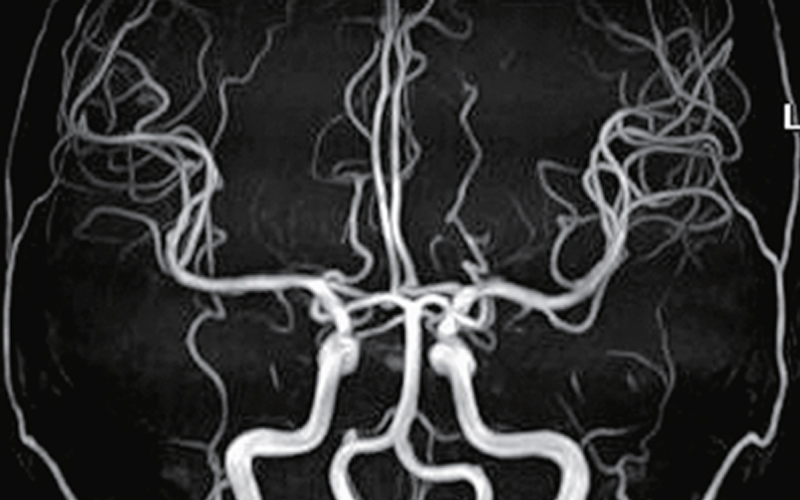

脳ドック・頸部動脈

脳卒中や認知症のサイン、気づいてますか?頭痛、頭重感、視力低下、物忘れ、日常動作の違和感は脳の病気のサインです。最新のMRI画像診断で、脳の腫瘍や動脈瘤、脳卒中のリスクとなる頸動脈の狭窄などを調べます。